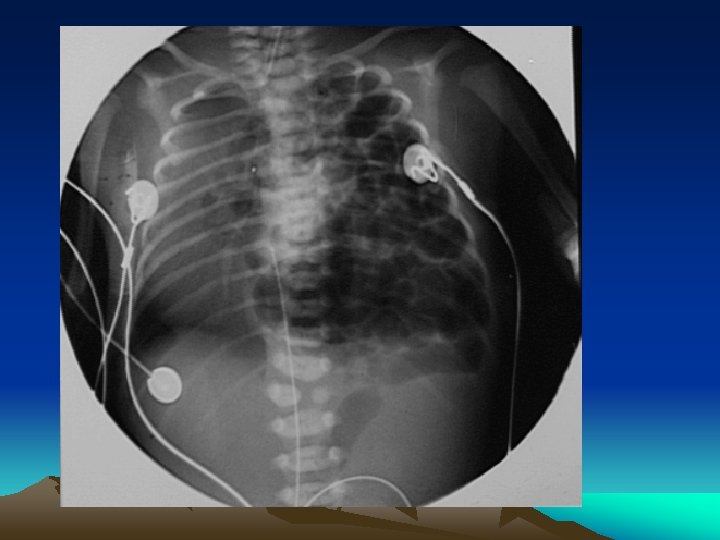

Bochdalek hernia • Called a postero-lateral diaphragmatic hernia. • The most common of CDH (95% ). • characterized by a hole in the postero-lateral corner of the diaphragm which allows passage of the abdominal viscera into the chest cavity. • The majority (80 -85%) occur on the left side of the diaphragm.

Presentation • Infants born with diaphragmatic hernia experience respiratory distress and failure due to both : pulmonary hypertension and pulmonary hypoplasia.

Diagnosis • This condition can often be diagnosed before birth (u/s). • X- ray chest • CT chest • Contrast study of the GIT

Treatment • It should be noted that: 1. CDH is considered a medical emergency not a surgical emergency 2. Optimization of the baby condition is very important before surgery 3. ECMO may be used for patient stabilization